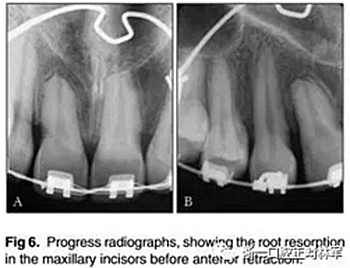

此時,拍攝隨訪的根尖片(圖6)。這些圖像表現(xiàn)出根吸收增加的證據(jù),特別是在先前已經(jīng)診斷出根部縮短的上頜中切牙中。因此,牙齒移動被暫停了90天,然后逐漸恢復(fù),每隔2個月進行一次正畸復(fù)診。